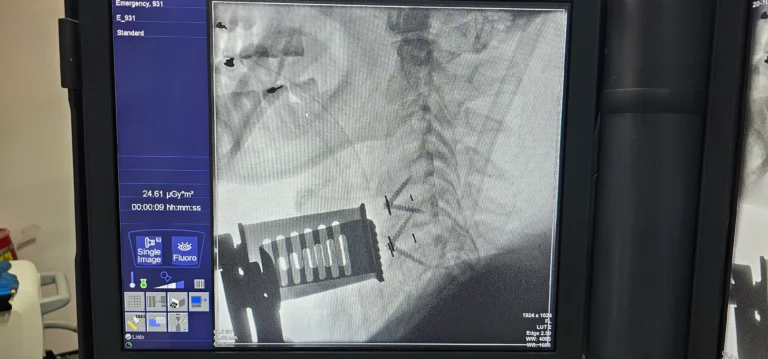

Specialist in the diagnosis and surgical management of conditions of the nervous system, with expertise in minimally invasive spine surgery, skull base procedures, neuro-oncology, and complex cranial and spinal pathologies.

- ✔ Minimally Invasive Spine Surgery

- ✔️ Minimally invasive spine surgery

- ✔️ AO Spine Trauma and Spine Courses

- ✔️ Comprehensive Spine Program – Zimmer Biomet (Miami)

- ✔️ Vertebral Stentoplasty for Osteoporotic Fractures – Case Report and Review